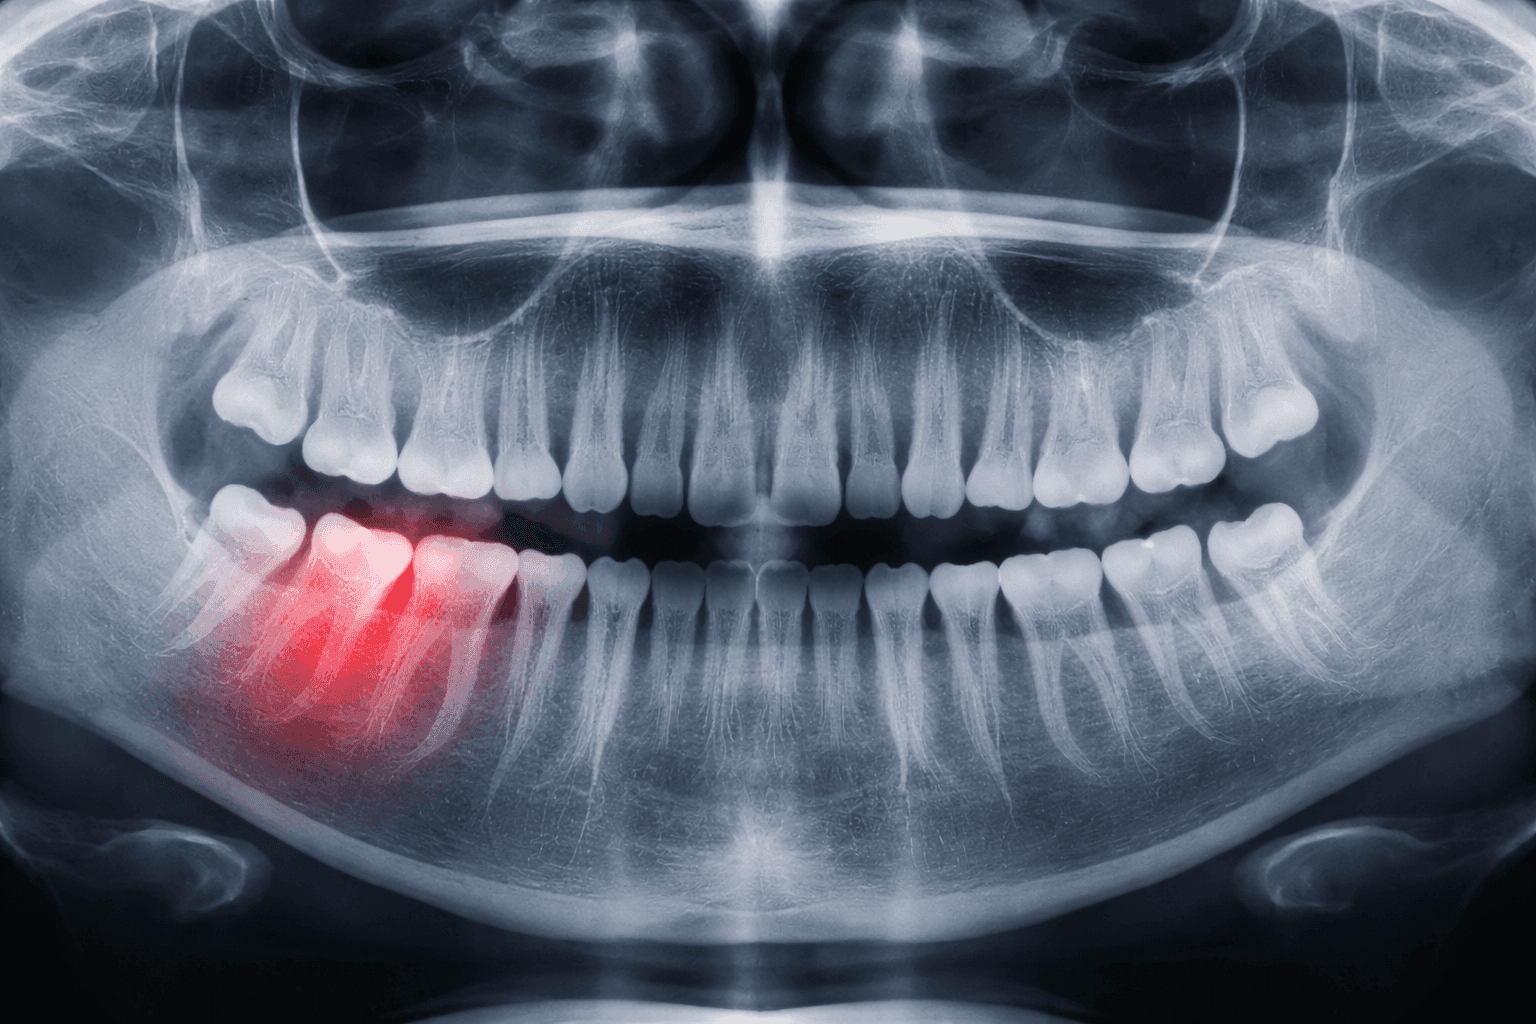

На то, что не прижился имплант или процесс остеоинтеграции нарушен, может указывать сохранение симптомов воспаления через неделю после операции. Боль, покраснение десны, отечность в первые пять дней — это нормально, как и небольшое повышение температуры. Но если после установки прошло больше 7–10 дней, но перечисленные недомогания не проходят, а нарастают, нужно поспешить к врачу. В отдельных случаях пациент ощущает лишь подвижность конструкции, остальных симптомов может и не быть.

Иногда отторжение импланта случается не в первый месяц после установки, а в отсроченном периоде, когда, казалось бы, стержень приобрел стабильное положение. Причиной этого могут стать бактериальные процессы, ошибки протезирования, травмы.